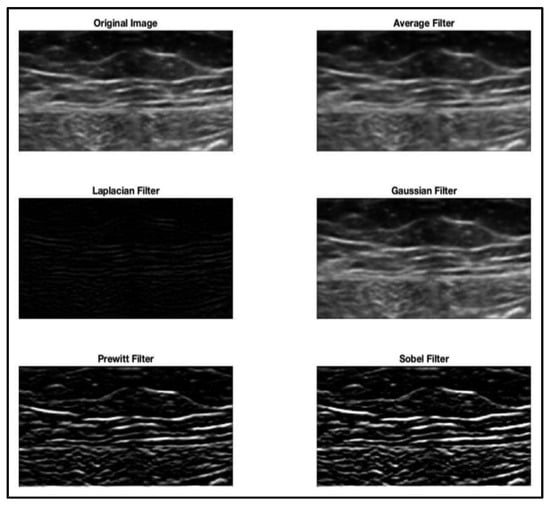

| Intensity-based/dimensional-based filtering | [3,6,12,17,28,54,70,86] |